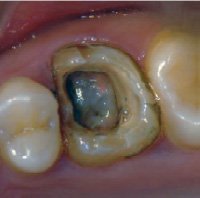

これらの銀歯と土台を除去してみると、内部が黒く変色していることが確認できました。変色部分と金属の被せ物を丁寧に除去し、金属を使用しない被せ物に置き換えました。